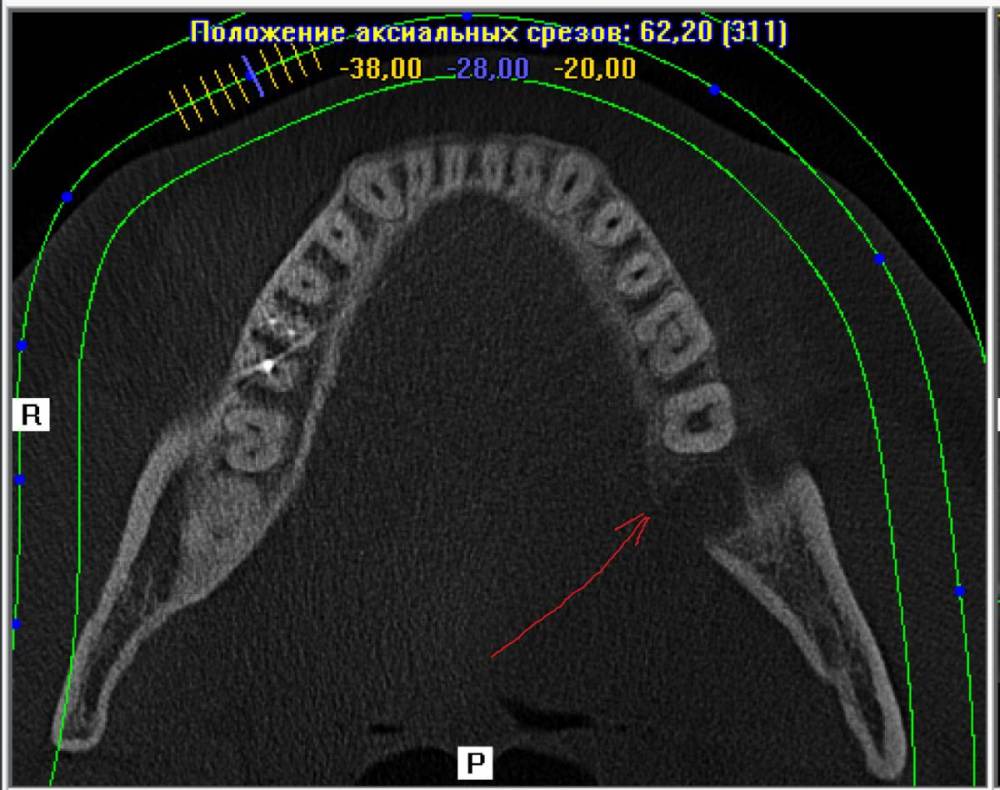

ЕвгенийЗ Опубликовано 24 июня, 2021 Автор Поделиться Опубликовано 24 июня, 2021 И если немного выше поднять плоскость, то как раз виден этот край альвеоллы(или как правильно?). Но он вроде как отколат что ли? Не могли бы взглянуть пожалуйста. Там где стрелочка, походу этот край и вылез. И еще плоскость по зубному ряду Ссылка на комментарий

ЕвгенийЗ Опубликовано 24 июня, 2021 Автор Поделиться Опубликовано 24 июня, 2021 Дополнение к последнему фото. Это вот эта плоскость Ссылка на комментарий

АнтонТЛТ Опубликовано 24 июня, 2021 Поделиться Опубликовано 24 июня, 2021 Да, это этот край альвеолы 1 Ссылка на комментарий